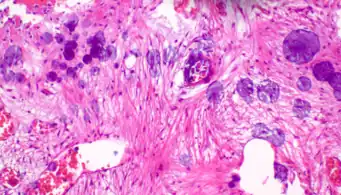

Cellulose contamination, in H&E stain and polarized light Cardiac muscle (bottom) with contamination from thyroid tissue (center)

Cardiac muscle (bottom) with contamination from thyroid tissue (center) Crush artifact from compression by forceps on the tissue sample